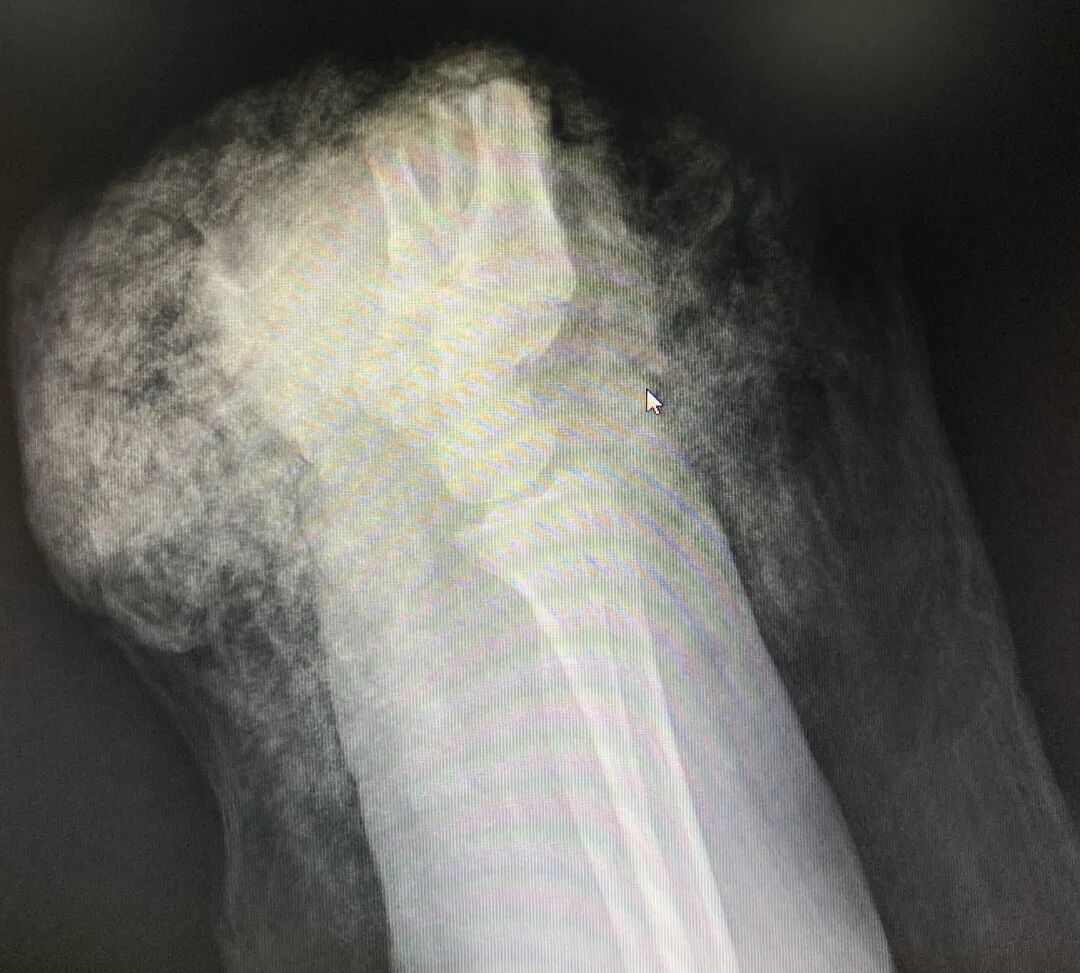

断掌正面CT图 断掌侧面CT图

5小时手术断掌残垣 “截”后余生

“因牵牛而导致断手的病例还是头一次看到。”树兰(杭州)医院手足显微外科黎斌副主任医师接诊后表示:“伤者由于手掌被麻绳勒紧,受到前后牵拉力同时作用而造成手掌骨头、肌腱及神经组织断裂,属于非常严重的旋转撕脱离断伤。”

黎斌副主任介绍介绍,手足显微外科经常会接诊被机器或者刀具砍伤的手部受损,断面比较整齐,但张奶奶这种撕扯伤有很多缺损组织,因拉扯被抽出的肌腱长度达20多厘米,比砍断更严重,大大增加了再植手术的难度,因此当时伤者送到医院时已经面临截肢的危险。